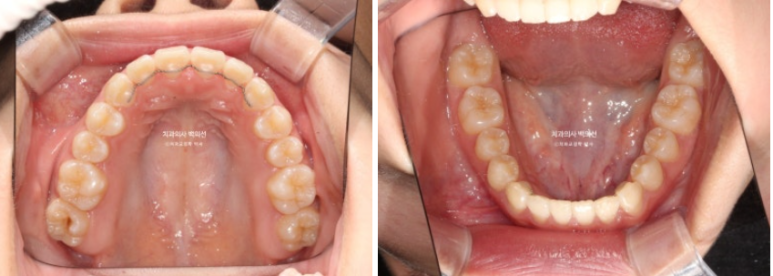

24.01

23년 10월부터 24년 1월까지 악궁확장 후 모습입니다.

악궁확장이 성공하면 앞니 사이가 벌어지죠.

이틈은 사진처럼 몇주내에 자연스럽게 다시 닫히게 됩니다.

이제 뼈를 넓혔으니 치아를 배열해야합니다.

악궁확장장치 제거 후 인비절라인 장치제작에 들어갑니다.

인비절라인 장치를 기다리는 6주의 시간동안 악궁폭이 좁아지지 않도록 임시 유지장치를 만들어서

껴줍니다.

24년 2월부터 본격적으로 인비절라인 장치를 끼기 시작했습니다.